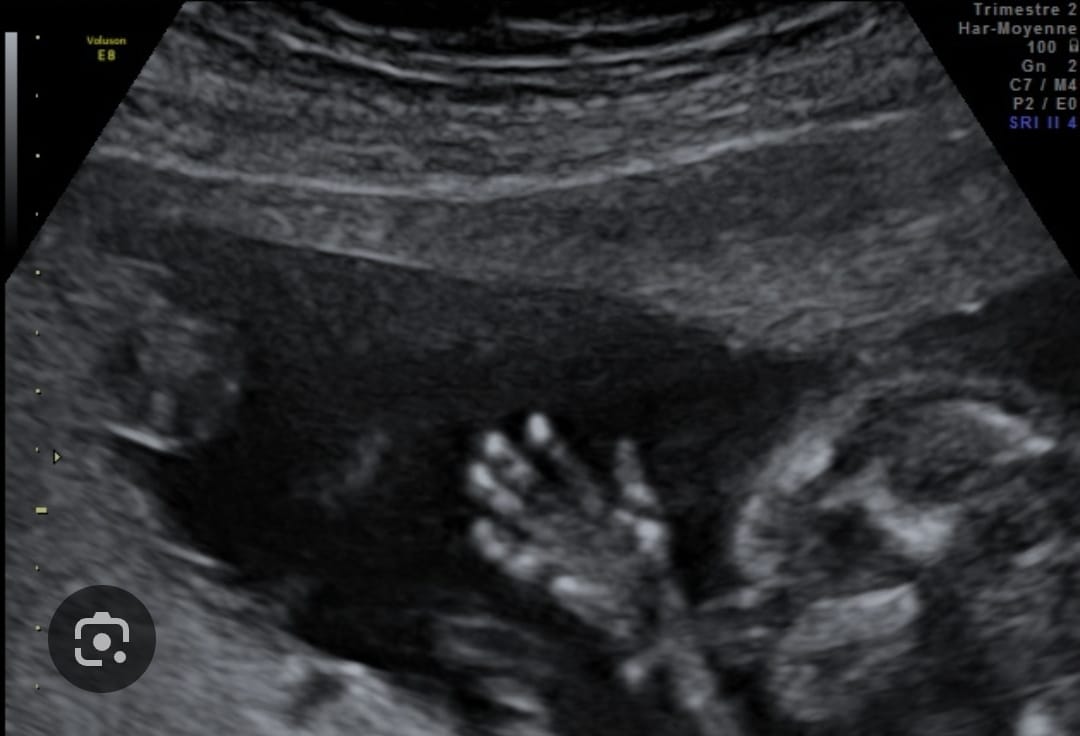

Ci-dessous quelques images de ce que l’on peut observer à la T2 :